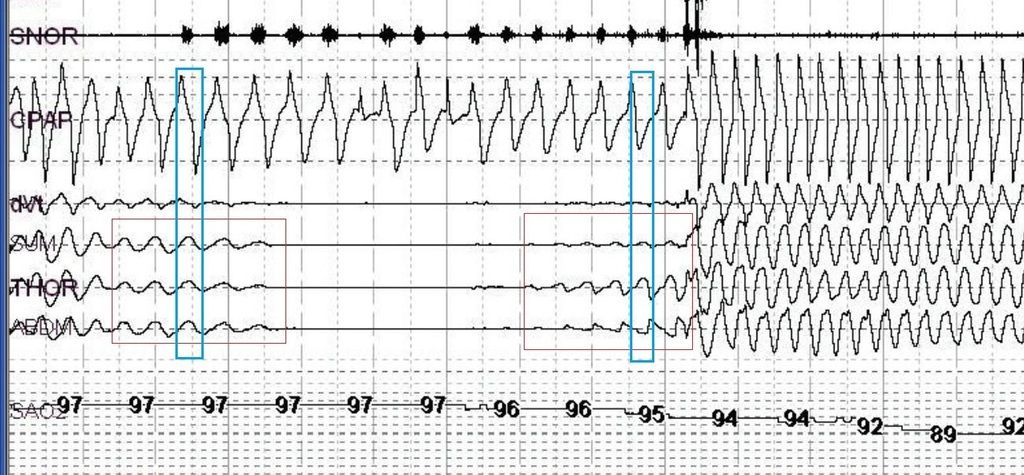

An 80-year-old man with severe central sleep apnea due to Cheyne-Stokes breathing (AHI 41.2) caused by severe cardiac failure underwent a trial of adaptive servo-ventilation (ASV) by full face mask after failure of a fixed CPAP trial. Recommended procedure was closely followed and the ASV device activated normally during central apneas. Initial settings were EEP 5, PSmin 3, PSmax 15 on room air. The device did not capture the thorax or abdomen, as shown by lack of change in respiratory inductive plethysmography, despite expected mask pressure waveforms. Snoring was also detected during apneas with device activation. Desaturation continued, followed by arousals during hyperpnea. On the device, the patient clearly slept for 1-3 epochs during the central apneas only to awaken during hyperpnea. We hypothesize that the failure to capture may have resulted from “reverse” obstructive apnea, possibly due to glottic closure during ASV activation. We suggest that earlier manual adjustments to ASV in cases such as ours, prior to waiting for the recommended 20 to 40 min of sleep, may be appropriate in selected patients.

In the epochs presented, the abdominal and thoracic belt waveforms have become paradoxical, making this a "mixed" event (the latter portion being obstructive):

By paradoxical, we mean that in normal breathing, thoracic, abdominal and sum channels are all in sync. When obstruction occurs and breathing is attempted, thoracic effort rises, but since no air can be inhaled, the abdomen paradoxically sucks in and creates an opposite deflection. The sum channel (sum of the thoracic and abdominal belts) becomes dampened as the two waveforms begin to cancel each other out:Morbius wrote:In the epochs presented, the abdominal and thoracic belt waveforms have become paradoxical, making this a "mixed" event (the latter portion being obstructive):